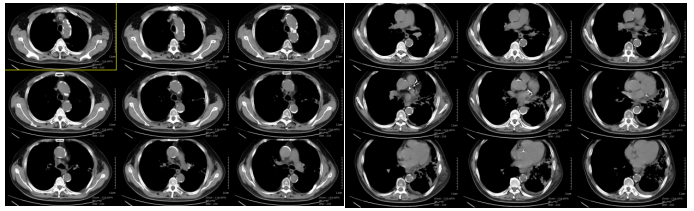

Chest CT on June 11, 2024 (4 months after carbon ion therapy):Left lung tumor 4.3 × 2.0 × 4.0 cm